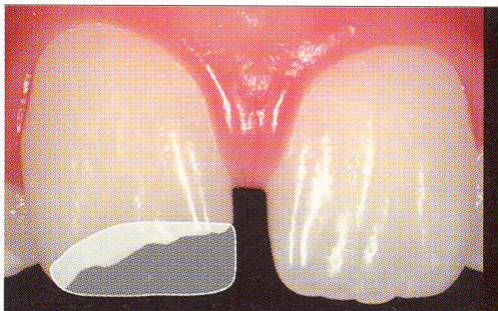

一応差し歯にしましたが、歯茎の状態はよくはありません。

とりあえず希望を入れて差し歯にしたような感じです。